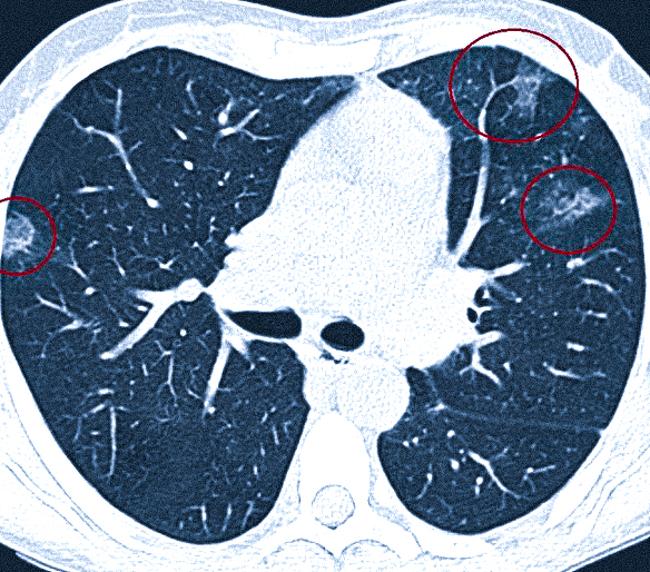

Видно ли пневмофиброз на КТ легких

Компьютерная томография является золотым стандартом в диагностике пневмофиброза. Данное исследование позволяет с высокой вероятностью выявить рубцовые изменения, определить точное положение, размеры, форму и прочие характеристики. КТ основано на применение рентгеновского излучения для создания черно-белых изображений изучаемой области, на которых участки различной плотности отражены изменением интенсивности затенения.

КТ признаки пневмофиброзных изменений в легких

Компьютерная томография помогает выявить мельчайшие рубцы, образующиеся в области воспалений после их заживления. Такие образования могут встречаться после оперативных вмешательств.

На определенных стадиях фиброза можно наблюдать изменения, напоминающие «матовое стекло» в тех участках легочной ткани, где плотность повышена. Эти участки выглядят светлее по сравнению со здоровыми, так как с трудом пропускают рентгеновские лучи.

При широком распространении фиброза можно наблюдать «сотовое легкое», когда множественные кистозные полости располагаются в ряд. Эти полости заполнены воздухом, а их стенки значительно толще, чем нормальные межальвеолярные перегородки. Гистологическое исследование показывает, что данная структура состоит из соединительных тканей.

Изменения могут наблюдаться в пределах одного легкого или распространяться на обе стороны. Если фиброз локализован в пределах единичного сегмента дыхательной паренхимы, патологию называют очаговой. При распространении соединительной ткани в разных долях обоих легких диагностируют диффузный процесс. Чем больше процент поражения, тем серьезнее клиническая картина и хуже прогноз.